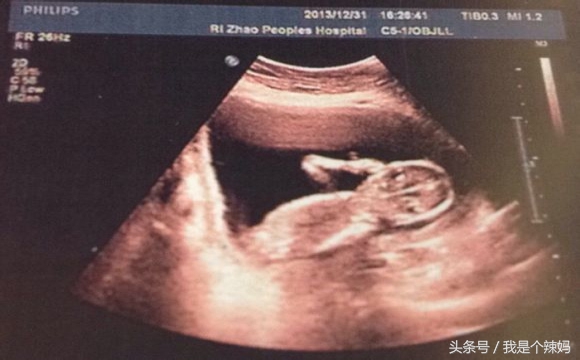

【B超查性别】

靠谱等级:如果是男宝宝的话,准确度会比较高(95%左右)如果是女宝宝就会低一点(85%左右准确度)

优点:多方向观察,实时成像。

缺点:超声受气体干扰很大,对于肠道等含气较多的器官,超声诊断准确率会降低,所以一般肠道检查使用肠镜。